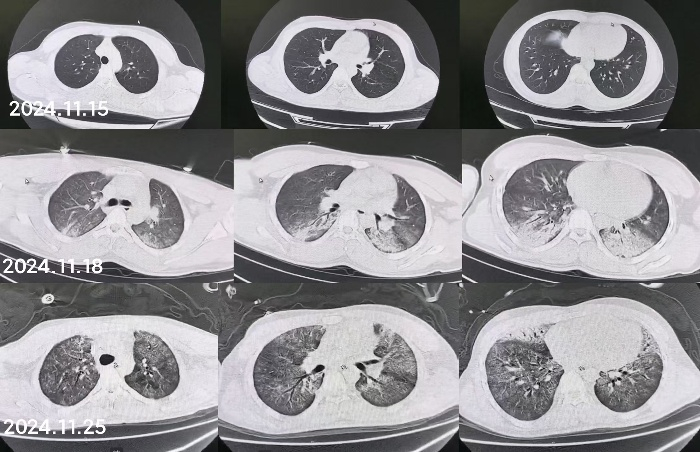

同时给予镇痛、镇静联合肌松,去甲肾上腺素泵入维持血压,俯卧位通气,B某入院后出现高热,经验性给予美罗培南联合万古霉素抗感染治疗,后降阶梯调整为哌拉西林他唑巴坦联合万古霉素治疗;C某抗感染方案为经验性使用万古霉素联合哌拉西林他唑巴坦治疗,痰培养出鲍曼不动杆菌后改为替加环素、头孢哌酮舒巴坦及万古霉素治疗;根据《刺激性气体中毒诊治专家共识》[5]中关于重症患者的治疗措施,同时给予2人泮托拉唑抑酸护胃,氨溴索、富露施化痰、甲泼尼龙抗炎、西维来司他纳及乌司他丁清除炎性介质,维生素C抗氧化、保肝、输血补液,纤支镜吸痰及肺泡灌洗,维持水电解质平衡及营养支持治疗,特别考虑到肺损伤情况,在使用有创通气时给予超保护性通气策略[5, 7];2人仍先后出现气胸、纵膈气肿,行胸腔闭式引流;持续V-V ECMO治疗15 d后,肺部纤维化不可逆转,高分辨率CT肺纤维化评分 > 75%(图 3、4),符合终末期肺病标准,有肺移植指征[8],经评估后2人顺利完成病变肺组织切除(图 5),双侧序贯肺移植,术后患者复查胸片肺部恢复正常(图 6),2位患者术后气管切管接呼吸机辅助通气,并给予泼尼松、他克莫司、吗替麦考酚酯抗排异治疗,其余根据病情给予万古霉素调节肠道菌群、抗感染、保肝、抗凝、呼吸康复锻炼等治疗,后顺利脱机、拔除气切套管,病情稳定出院,后续规律复查胸部CT(图 7)恢复良好。

| 图 3 B某发病15 d时胸部CT表现 |

| 图 4 C某发病15 d时胸部CT表现 |